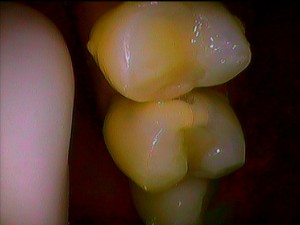

上のの写真では、しっかりと噛み合わせた上下の歯の写真ですが、長年使っている奥歯の磨耗などのすり減りで、前歯に負担がかかり、その結果として上下の前歯の同士の擦れにより、前歯の先端が磨耗してザラザラしてしまったようです。